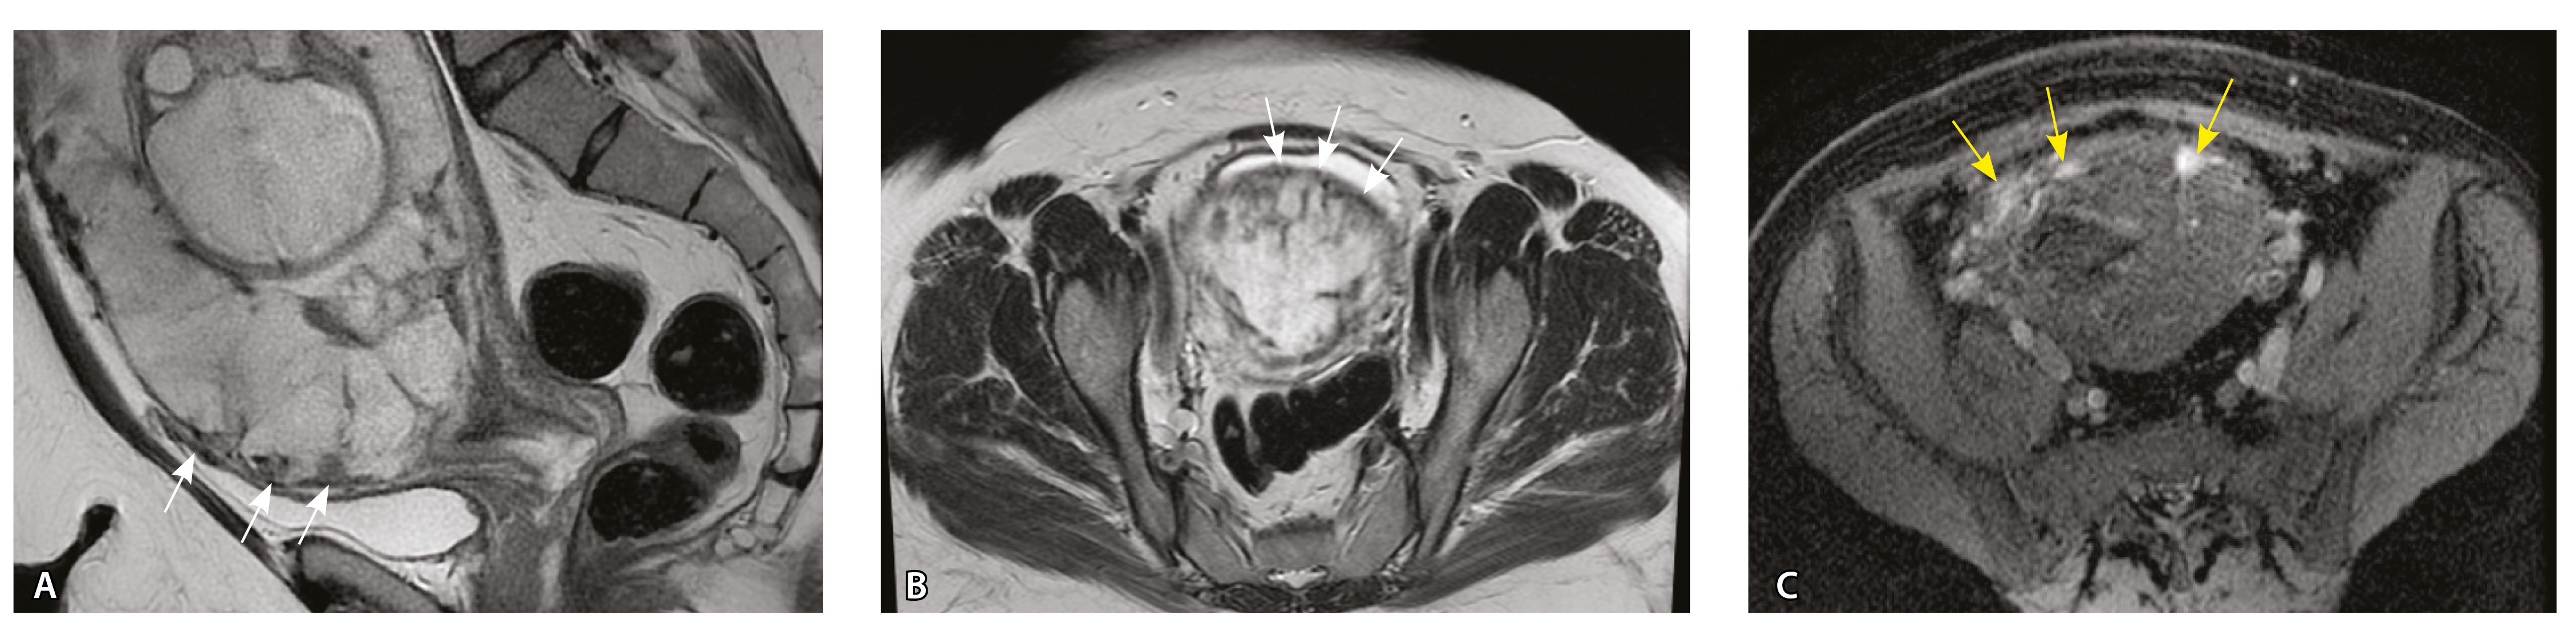

Сосуды 1-го типа. Единичные сосуды в миометрии и пограничных отделах в маточно-плацентарной области (рис. 2).

Рис. 2. Беременность 32 недели, центральное предлежание плаценты без признаков приращения. На магнитно-резонансных томограммах в режиме Т2-взвешенного изображения (Т2ВИ) в сагиттальной плоскости (А) и Т2ВИ с подавлением сигнала от жировой ткани во фронтальной плоскости (Б) видны мелкие ретроплацентарные сосуды, расположенные на границе плаценты и рубца на матке от кесарева сечения (белая стрелка) либо плаценты и миометрия (желтые стрелки; плацентарная площадка указана белой пунктирной линией). Фото микропрепарата: В – визуализируются мелкие артерии и вены в составе серозной оболочки, стрелкой указан слой мезотелия (окраска азокармином по Маллори; × 50); Г – маточно-плацентарный сегмент, стрелкой указан сосуд в толще миометрия на границе с плацентой (окрашивание гематоксилином и эозином; × 50)

Сосуды 4-го типа. Наличие крупных извитых анастомозирующих сосудов, преимущественно по поверхности матки (в составе серозной оболочки матки) в сочетании с выраженным истончением нижнего сегмента матки (рис. 10).

Рис. 10. Беременность 33 недели, pl. percreta, PAS 3a по FIGO. На магнитно-резонансных томограммах в режиме Т2-взвешенного изображения в сагиттальной (A) и фронтальной (Б, В) плоскостях определяется внутриматочная гиперваскуляризация (желтые стрелки) и гиперваскуляризация в области выраженно истонченного нижнего маточного сегмента, с наличием многочисленных анастомозирующих сосудов по поверхности матки (белые стрелки); стенка матки в данной области представлена ретроплацентарными сосудами

Сосуды 5-го типа. Наличие гиперваскуляризации за пределами матки по данным МРТ, на границе с мочевым пузырем с вовлечением его стенки, сосуды в области перешейка матки, параметрия, в том числе в сочетании с признаками фиброза, наличием рубцово-спаечных изменений и др. Можно предположить, что сосуды 5-го типа являются аналогом pl. рercreta PAS 3b, 3c (рис. 15).

Рис. 15. Беременность 34 недели, pl. percreta, PAS 3b по FIGO (A, Б), PAS 3c по FIGO (В). На магнитно-резонансных томограммах в режиме Т2-взвешенного изображения в сагиттальной (A, В) и аксиальной (Б) плоскостях определяется гиперваскуляризация в области выраженно истонченного нижнего маточного сегмента с распространением сосудов на заднюю стенку мочевого пузыря в области дна (белые стрелки), в область перешейка матки (желтые стрелки)